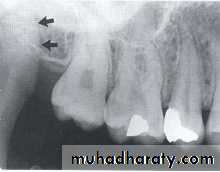

NUTRIENT CANALS

:

Nutrient canals carry a neurovascular bundle and appear as radiolucent lines of fairly uniform width. They are most often seen on mandibular periapical radiographs running vertically from the inferior dental canal directly to the apex of a tooth or into the inter dental space between the mandibular incisors.